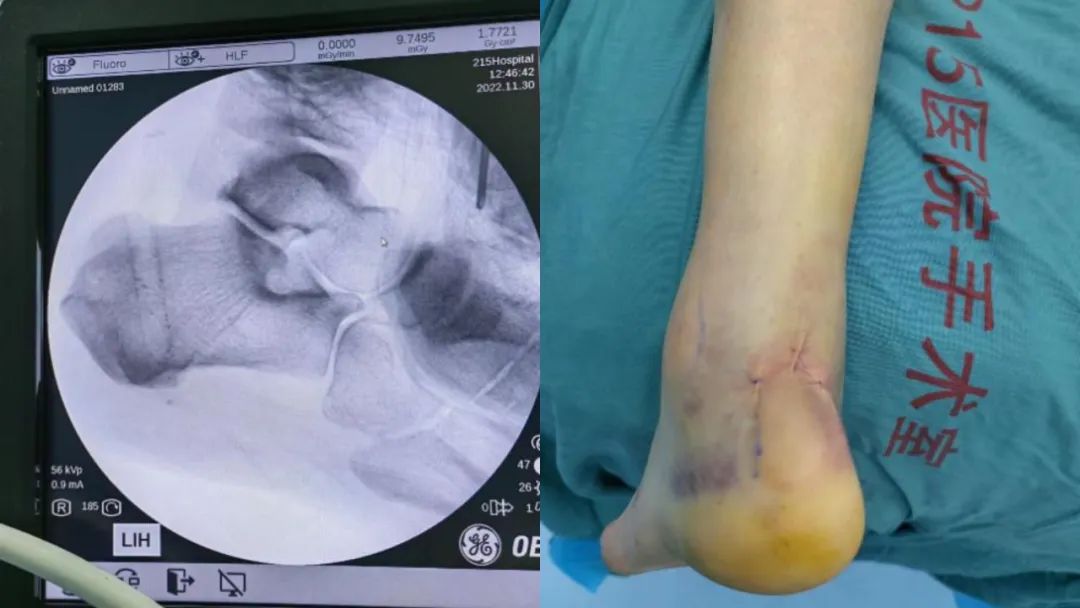

术前外观照,跟腱断端明显 术前MRI图像

术中关节镜下操作

术后即刻照片